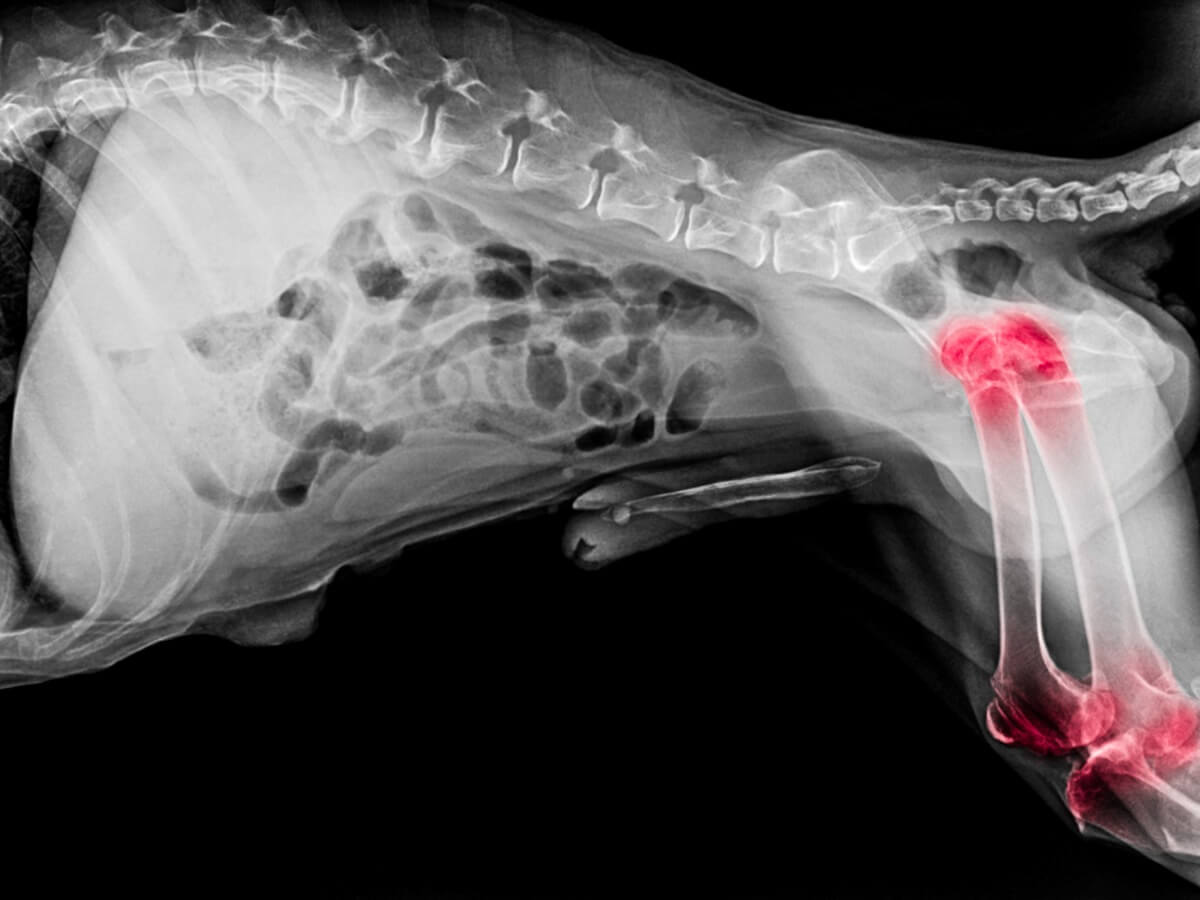

L’arthrite chez le chien

L’arthrite est un problème articulaire causé par l’enflure et la sensibilité des articulations. Parmi les symptômes les plus courants chez les chiens, figurent les suivants :

- Réduction de l’activité physique

- Raideur des articulations

- Difficulté à effectuer des mouvements tels que monter et descendre des escaliers, s’allonger ou se lever

- Maladresse en marchant

- Inflammation visible dans les articulations

- Déformation articulaire

Aucun chien n’est exempt de souffrir de cette maladie, mais elle est très fréquente chez les chiens de grande race. En plus de cela, il s’agit d’une pathologie chronique, mais si elle est diagnostiquée tôt et si l’alimentation est adéquate, la qualité de vie de l’animal peut être améliorée.